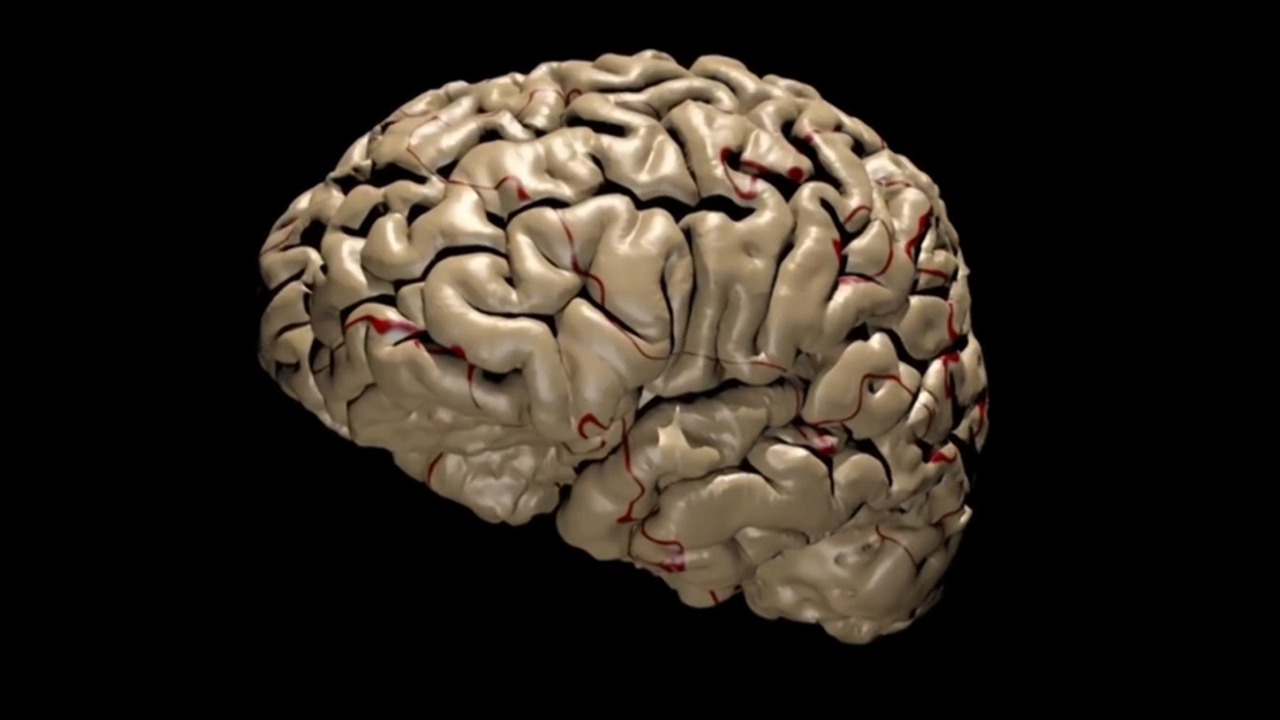

المهمة الصعبة لقراءة الدماغ البشري Bbc News عربي

المهمة الصعبة لقراءة الدماغ البشري Bbc News عربي